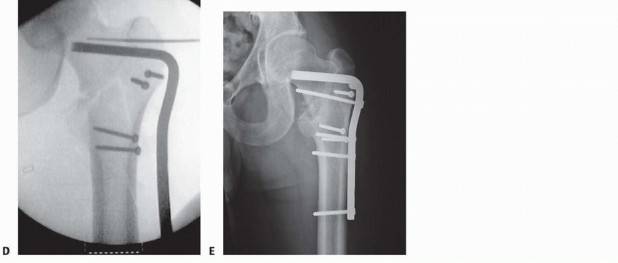

### TECH FIG 3 • Implant insertion. A. Lag screw and side plate on inserter. B. Placement of side plate. C. Implant in place. D. Traction released. E. Fracture after compression. A triple reamer is used to prepare the channel in the lateral cortex, neck, and head for the lag screw and side plate barrel. The reamer is set to 5 mm less than the measured lag screw length to ensure that the subchondral bone in the femoral head is not violated during reaming. The triple reamer is then advanced and withdrawn under fluoroscopic guidance. It is important to use fluoroscopy during reaming to ensure that the guide pin is not bonded to the reamer and inadvertently advanced into the pelvis. The channel is reamed to its proper length and removed under fluoroscopic guidance, ensuring that the guide pin is not withdrawn with the reamer. An obturator may be used to help prevent the pin from backing out. Occasionally, the intact lateral wall of the proximal femur may be fractured by the triple reamer. If this occurs, the fracture is essentially converted into a transverse or reverse oblique pattern (AO/OTA type 31-A3), and excessive fracture collapse will occur if fixed only with a sliding hip screw. In these cases, the proximal lateral wall may be buttressed with the addition of a trochanteric stabilizing plate in conjunction with a sliding hip screw. Alternatively, the decision may be made to convert to an intramedullary device for fracture fixation. ### Implant Insertion A two- to four-hole side plate is usually chosen for fixation ( TECH FIG 3). Multiple clinical and cadaveric studies have shown no difference in the strength of implant fixation with side plates with more than four holes. 3, 10 The implant is set up according to the manufacturer's specifications. The cannulated lag screw is then inserted over the guide pin with a centering sleeve to ensure proper positioning. Careful sizing of the lag screw length is required, as noted earlier, to ensure that fracture compression does not lead to excessive screw length and lateral hardware prominence. 409 Fluoroscopy and manual fracture palpation are used to ensure that the fracture is not displaced (rotated) while the lag screw is inserted. If the fracture is displaced by the insertion of the lag screw, it is removed, a derotation screw is added, the channel is tapped, and the lag screw is reinserted. Peritrochanteric fractures of the right hip tend to displace to an apex posterior angulation as the lag screw is turned clockwise during insertion, whereas left hip fractures tend to displace to an apex anterior angulation owing to the anatomic configuration and subsequent tensioning of the hip capsule with screw insertion. With the lag screw inserted to the desired depth within the femoral head on the AP and lateral fluoroscopic projection, its relation to the lateral cortex is checked to ensure proper length. Ideal position of the distal tip of the screw is approximately 5 to 8 mm deep to the lateral cortex. The side plate is then slid over the lag screw and inserter so it is seated on the lateral cortex, and the guide pin (and derotational pin if used) is removed. Traction is released at this point to allow slight impaction of the fracture in the axial plane. Cortical screws are inserted to secure the plate to the femoral shaft. If appropriate for the fracture pattern, the lag screw compressing screw is then inserted into the barrel of the lag screw and tightened to compress the fracture in the plane of the lag screw, under fluoroscopic guidance. The compression screw may be removed in certain cases. If the fracture is oriented such that weight bearing will cause compression at the fracture site, it is reasonable to remove the compression screw. It is mandatory to use and retain the compressing screw in paralytics, where there is no resting joint reaction force, and implant disengagement can occur with postoperative transfers. With the compression of the fracture complete, the alignment and implant position are checked once again with fluoroscopy. 1. ## Blade Plate ### Approach A lateral approach is used, as described earlier. Although the incision is more proximal, and angles toward the anterior superior iliac spine, the trochanteric block must be exposed and interval between tensor and gluteus medius must be exploited in order to visualize anterior neck. ### Preparation and Implant Insertion With the lateral femur and trochanteric block exposed, if a direct reduction is desired, a soft tissue-sparing reduction of the trochanteric block to the proximal femur is secured with pointed bone clamps and K-wires or small lag screws ( TECH FIG 4). Alternatively, an indirect reduction can be employed, relying on the proper position of the blade within the proximal segment to reduce the fracture when the plate is brought onto the shaft. Guide pins are then introduced into this reconstructed segment to facilitate proper seating of the chisel for the blade plate. The first pin is placed anterior to the femoral neck and secured into the anterior femoral head to demonstrate the femoral anteversion. The second pin is placed with the use of an angled guide and/or fluoroscopy near the tip of the greater trochanter and directed into the femoral head at a 90-degree angle to the femoral shaft. The chisel is inserted parallel to the two guide pins, just distal to the second pin. Care must be taken to maintain the correct alignment of the chisel with the shaft of the femur because this determines the flexion-extension of the fracture, which is fixed once the blade plate is inserted. The chisel is directed so as to pass through the center of the neck and seat in the inferior portion of the femoral head. Because of the anterior translation of the femoral head on the shaft, the insertion site is in the anterior half of the trochanter. The position of the chisel should be constantly checked with fluoroscopy before and during its insertion. The chisel is carefully removed and the appropriate-length blade plate is inserted and gently seated into the proximal fragment. The insertion should be frequently checked with biplanar fluoroscopy to ensure that the blade follows the path made by the chisel. Once the blade is seated, the most proximal screw is placed through the implant into the medial cortex of the proximal femoral neck, rigidly securing the implant to the proximal fragment. Fracture reduction is now achieved by bringing the plate to the shaft and controlling length and rotation. If needed, a femoral distractor may be used as a reduction tool. The distractor should be fixed to the lateral aspect of the femur, with the proximal pin in the head and neck fragment and the distal pin placed distal to the end of the plate. Distraction is applied across the fracture to improve fracture alignment and length through soft tissue tensioning. A bone clamp is loosely applied to the distal femoral shaft fragment and plate to counteract the tendency for the fracture to be reduced into varus with the femoral distractor. Pointed reduction clamps are used to reduce comminuted fragments to the plate without stripping them of soft tissue attachments. Fracture reduction is checked with fluoroscopy. If fracture alignment is acceptable, the distraction is taken off to allow fragment settling and fracture compression. The plate is then fixed to the shaft fragments with screws in the standard manner, and lag screws are inserted where the pointed reduction clamps were previously placed. The final fracture alignment and length, as well as the femoral head, are examined with fluoroscopy to ensure proper fracture reduction and to make sure that there has been no head penetration by the implant. 410

### TECH FIG 4 • Blade plate insertion. A,B. Preoperative AP and lateral radiographs of a type 31-A3 fracture in a 28-year-old man. C. Chisel inserted after femoral head and neck and trochanteric block were secured with lag screws. D. Insertion of blade plate. E. Postoperative AP radiograph. -